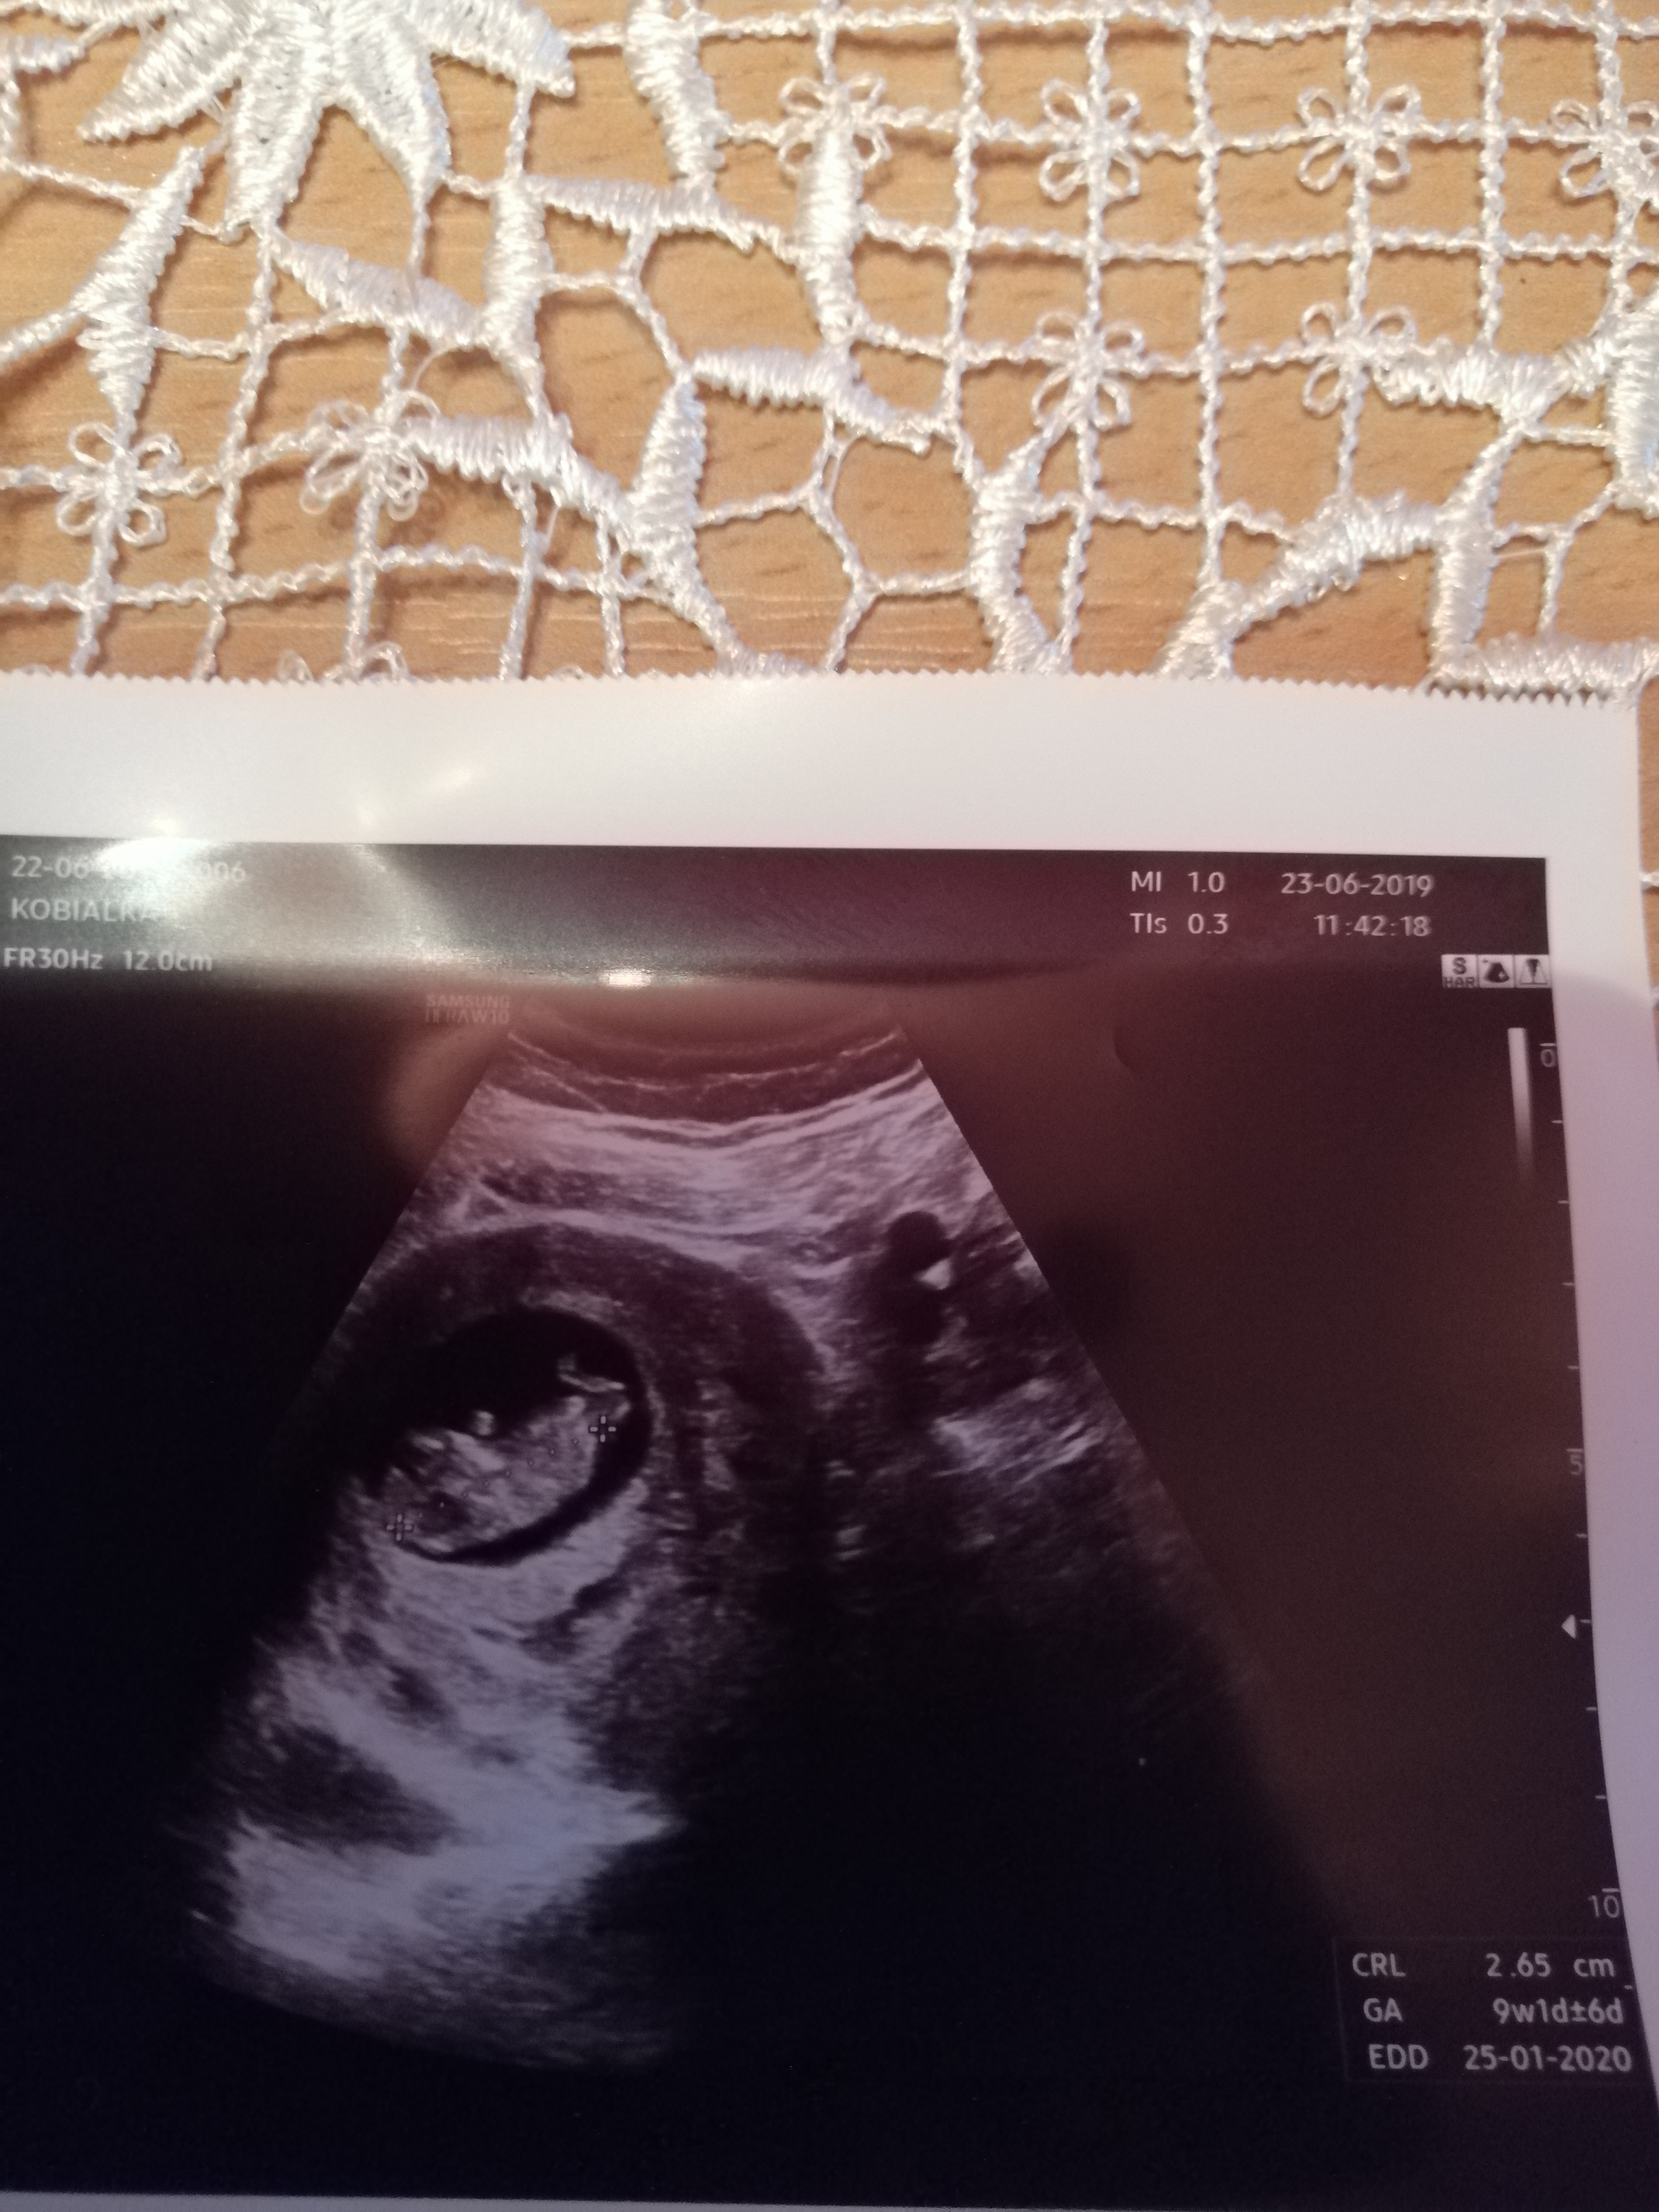

Ostatni raz 23.07.Ja jeżdżę do szpitala w Lublinie zawsze w niedzielę bo wtedy dyżur na izbie przyjęć ma mój doktor i robi mi wszystkie badania na NFZ. Moje dzieciątko wtedy miało 9w1d i crl 2,65cm.A twoje?Noo. A kiedy byłaś ostatnio na wizycie? Ile dzidziuś już mierzył?:-)

Ostatni raz 23.07.Ja jeżdżę do szpitala w Lublinie zawsze w niedzielę bo wtedy dyżur na izbie przyjęć ma mój doktor i robi mi wszystkie badania na NFZ. Moje dzieciątko wtedy miało 9w1d i crl 2,65cm.A twoje?

PowodzeniaMoja ostatnia wizyta tydzien temu 9+5 tc i maleństwo miało 3,1 cm jakoś tak. Jutro mam kolejną wizytę:-)